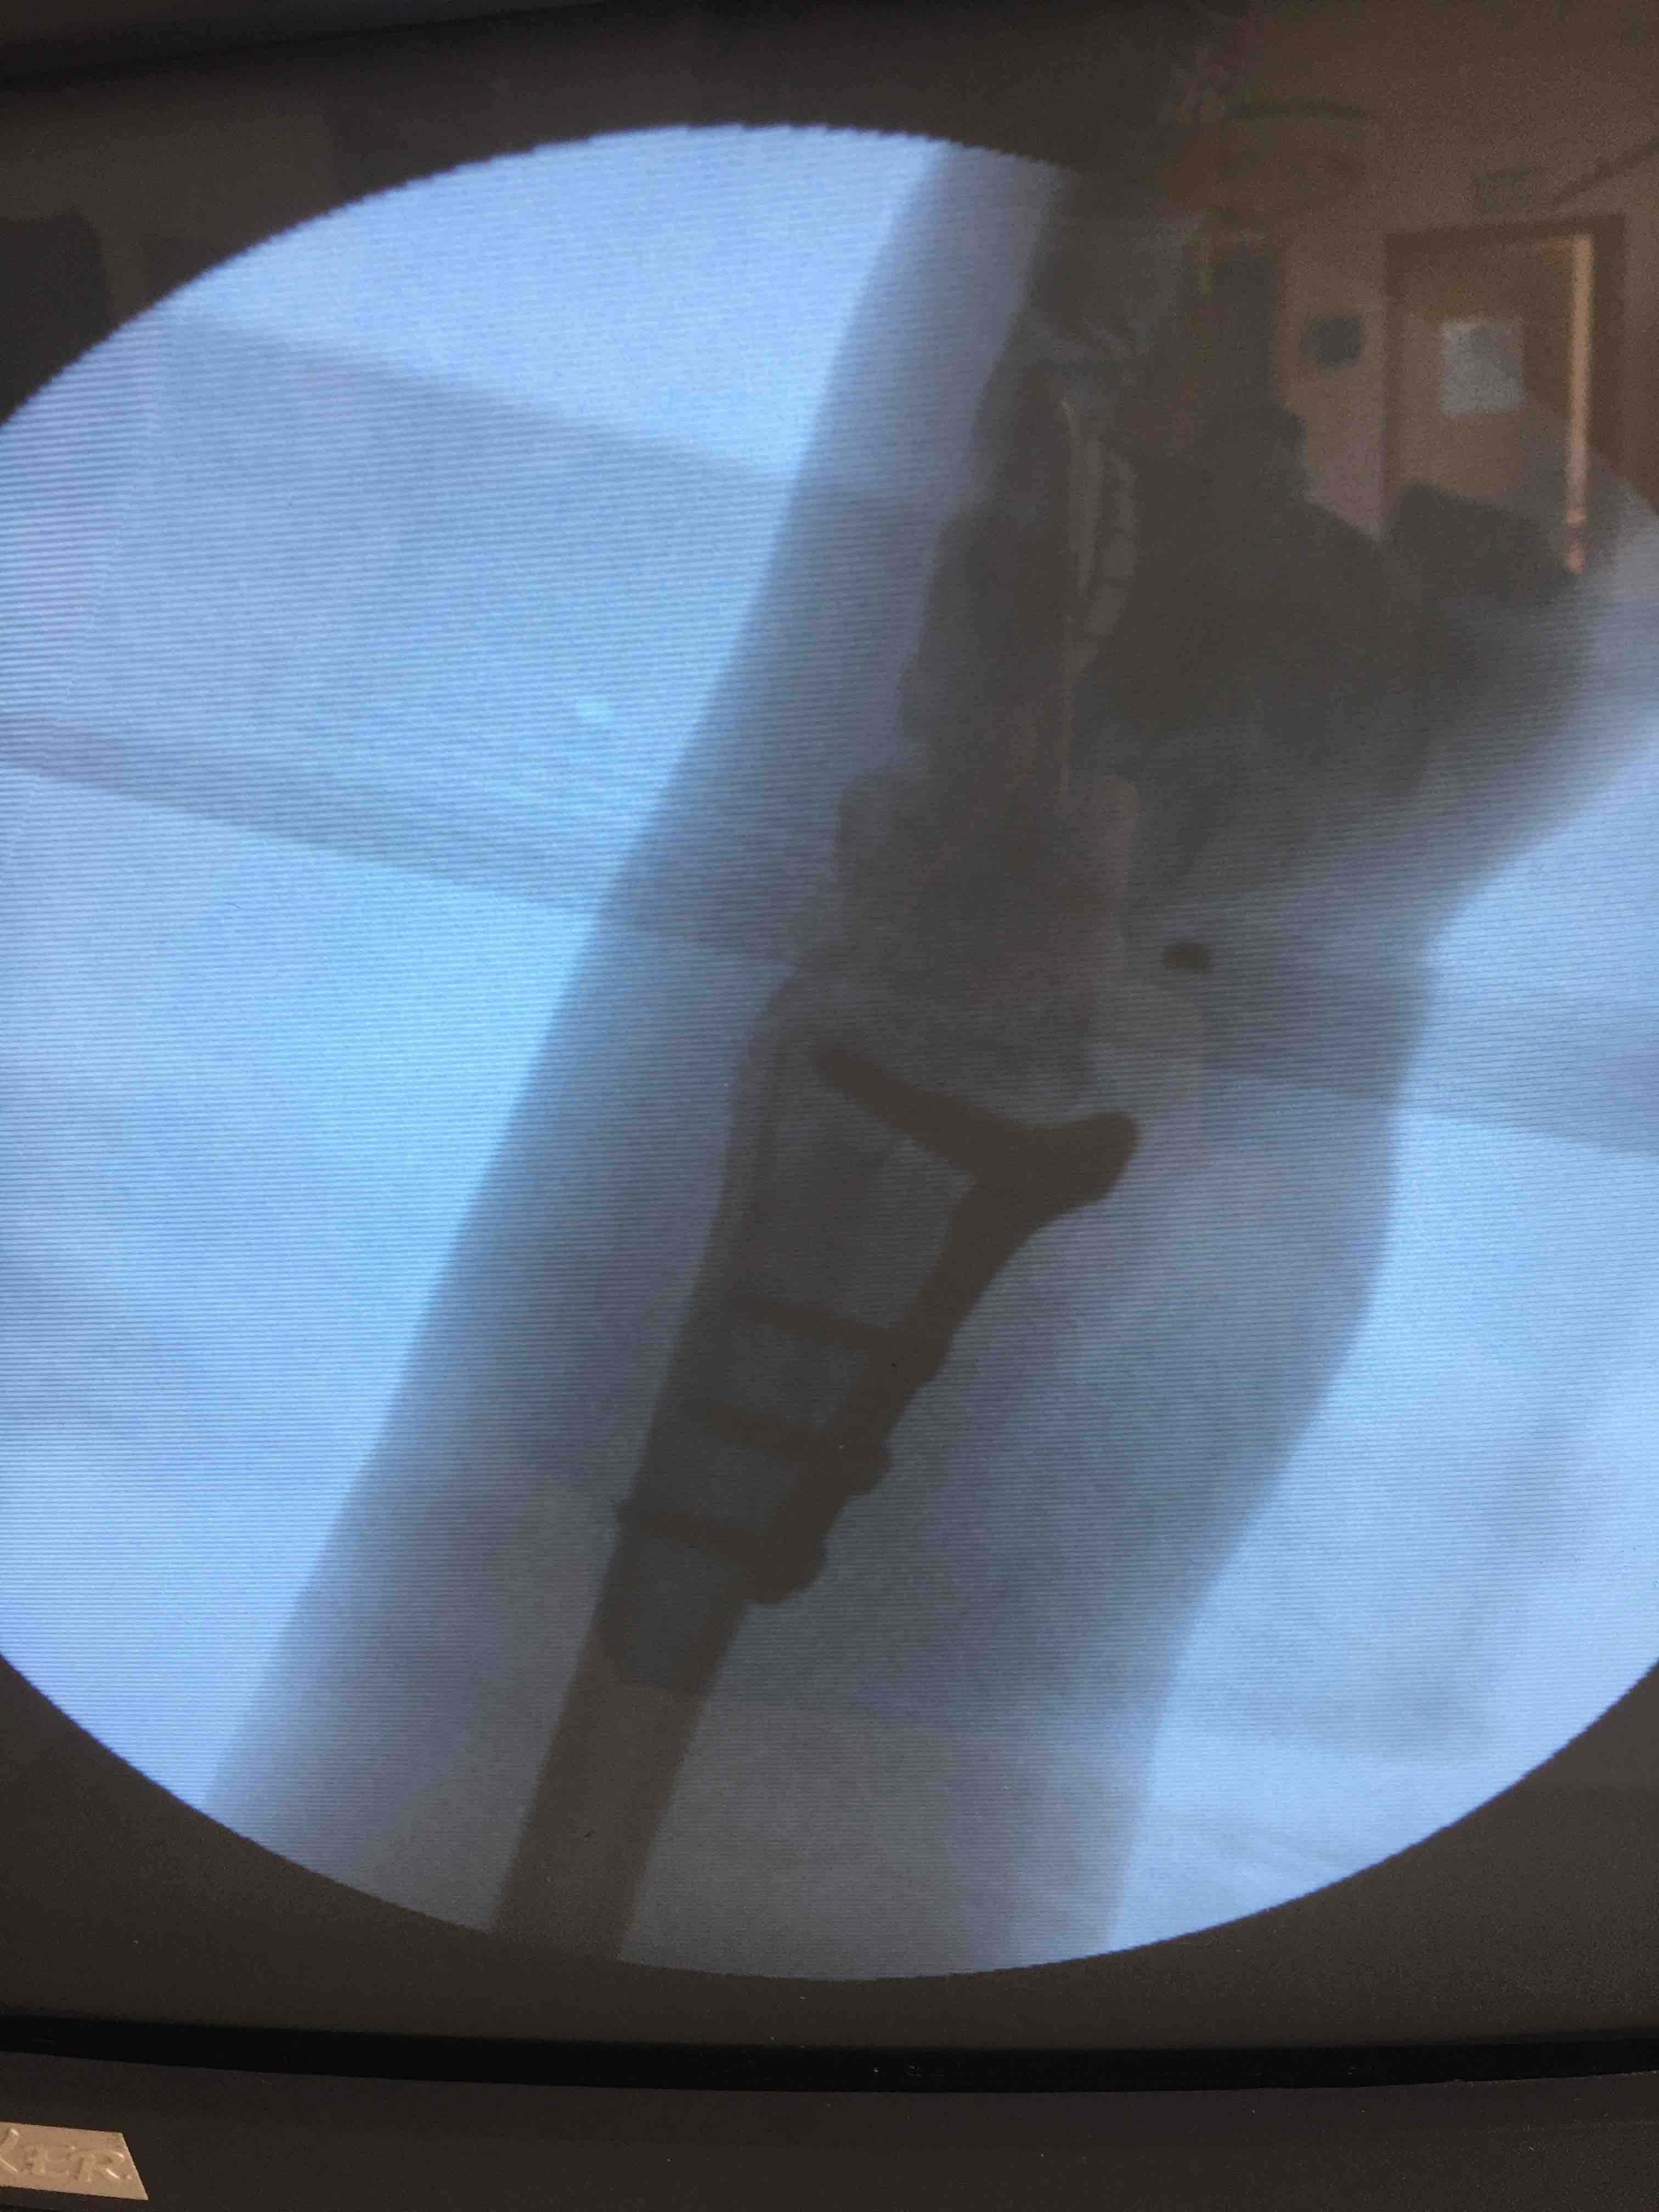

在臂丛下行切复内固定术,术后抗炎消肿等处理。

术后复查